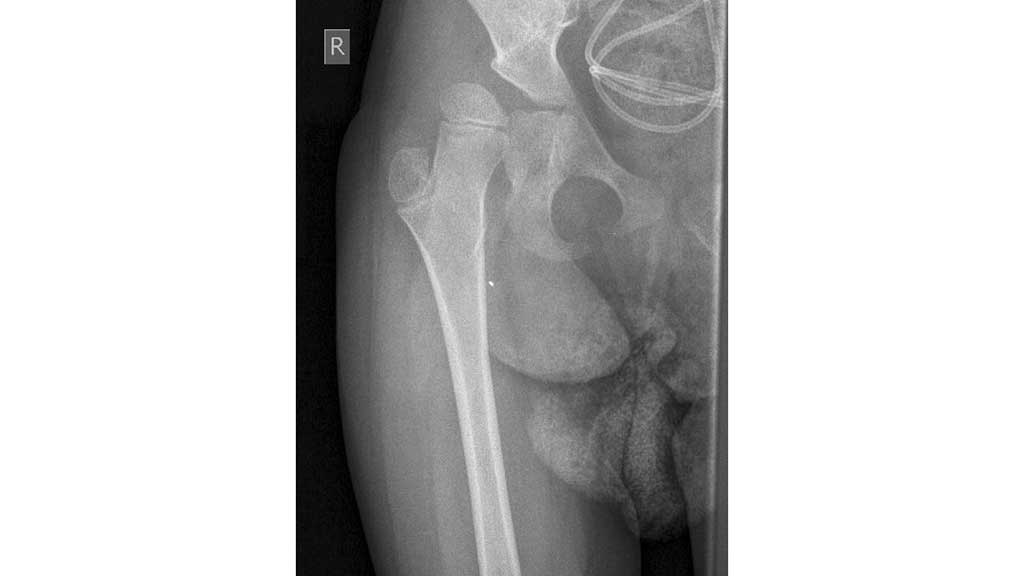

Annas Röntgenbild zeigte nach sechs Wochen eine gute Konsolidierung: Im Rahmen der Therapie begann die Fünfjährige mit dem Stehen und der Gewichtsverlagerung im Stand (Abb. 11). Parallel zur Vertikalisation erfolgten die Orthesenkontrolle und ‑nachpassung, zudem wurde der NF-Walker überprüft.

Inzwischen ist seit der Operation mehr als ein Jahr vergangen. Die Hüfte hat sich gut entwickelt (Abb. 12). Anna ist mittlerweile sechs Jahre alt. Sie kann wieder bis zu einer Stunde stehen, hat Spaß an der Fortbewegung im NF-Walker und schläft durch. Laut Mutter gibt Anna keinerlei Beschwerden mehr im Handling und beim Transfer an. Auch die Pflege gestaltet sich dank der verbesserten Abduktion einfacher als vor der Operation. Für den Spätsommer dieses Jahres ist die Metallentfernung geplant.